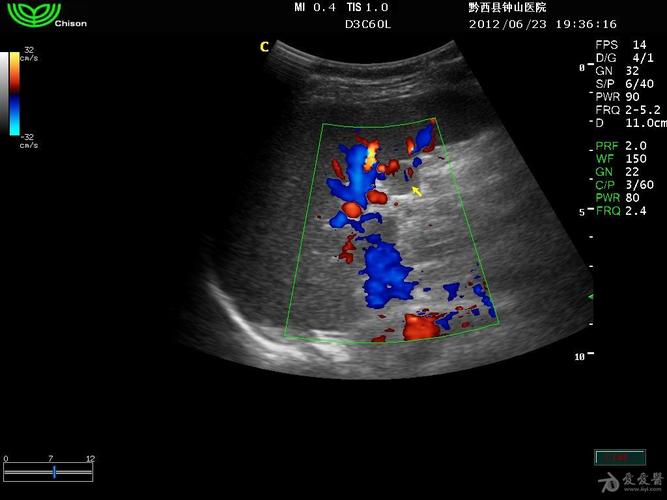

请看看这是副脾吗 - 超声医学讨论版 - 爱爱医医学论坛 - 爱爱医医学

副脾超声图片

副脾彩超图片